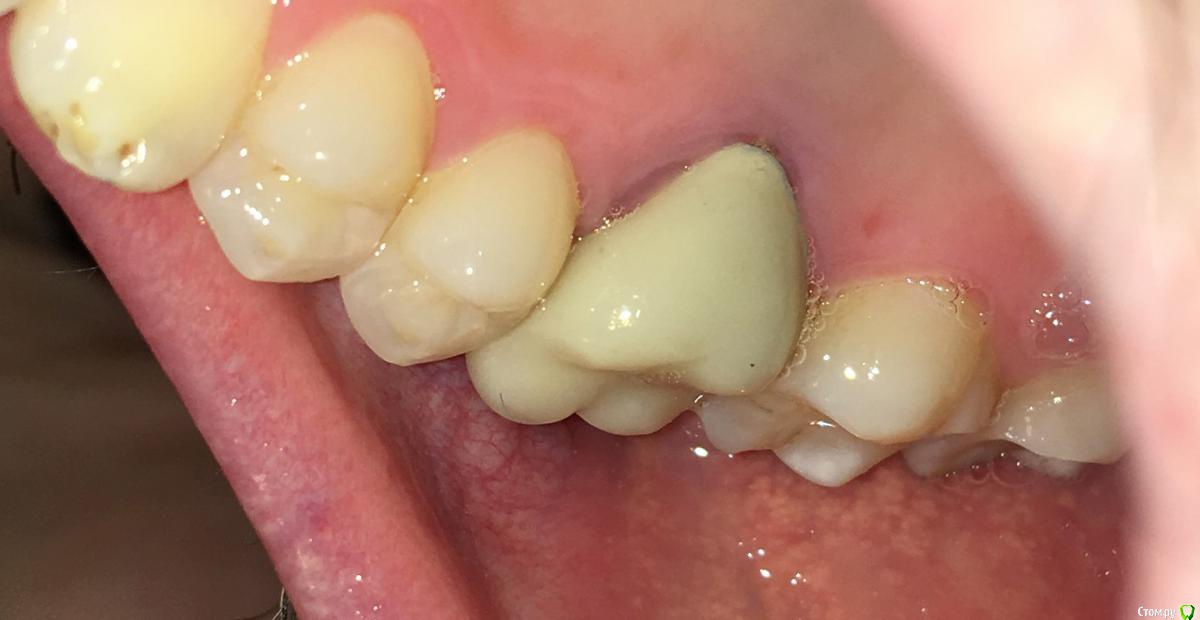

MichaelV Опубликовано 17 октября, 2019 Автор Поделиться Опубликовано 17 октября, 2019 (изменено) Вот какая ситуация на сегодня.Забыл сказать, что в прошлый прием (неделю назад, когда я написал этот пост), мне немного подточили опорный зуб (возможно и часть вкладки, но не уверен) около десны. Изменено 17 октября, 2019 пользователем MichaelV Ссылка на комментарий

chervoncevdaniil Опубликовано 17 октября, 2019 Поделиться Опубликовано 17 октября, 2019 Чуда не произошло 1 Ссылка на комментарий